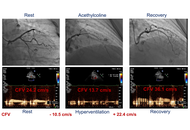

Pulmonary congestion and coronary microvascular dysfunction are central to hemodynamic adaptation before and after transcatheter aortic valve replacement (TAVR). This perspective proposes an exploratory, physiology-anchored framework that integrates lung ultrasound (LUS) and transthoracic Doppler of the left anterior descending artery (LAD) to track these domains on the same bedside platform. A concise anterior four-site LUS sampling captures early, posture- and stress-dependent interstitial congestion, while LAD Doppler provides a non-invasive window on resting diastolic coronary flow velocity (CFV) and CFV reserve (CFVR). In severe aortic stenosis, valve unloading with TAVR typically reduces filling pressures and restores diastolic coronary flow, though CFV and CFVR responses vary with the balance between myocardial oxygen demand and improved hyperemia. Interpreting these signals alongside standard echocardiographic indices (E/e’, LAVI, SPAP, and Doppler velocity index) ensures physiological coherence and avoids misattribution. Rather than focusing on numeric thresholds, this approach emphasizes trajectories—how B-lines, CFV, and CFVR evolve from baseline to post-TAVR follow-up. Concordant improvement supports decongestion and microvascular recovery, whereas discordance prompts investigation of right-sided or extra-cardiac mechanisms. Readily implemented with existing echocardiographic equipment, the combined LUS-LAD strategy offers a scalable, hypothesis-generating tool to explore pulmonary-coronary interactions, guide decongestive and anti-ischemic therapy, and inform future feasibility and reproducibility studies in the TAVR population.